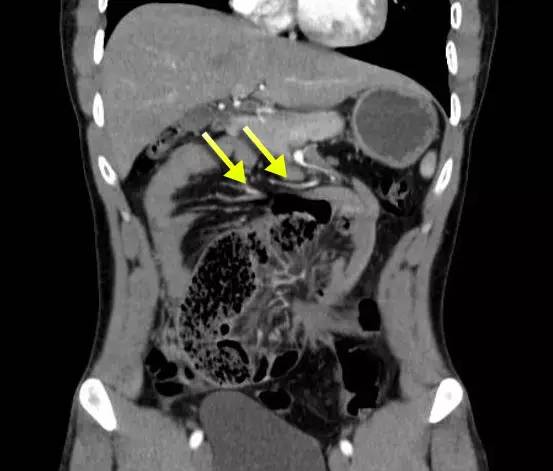

下图:右侧十二指肠旁疝,疝囊位于肠系膜主干的右侧,肠系膜的空肠支(黄箭)环绕至肠系膜上动脉主干的右后方为其供血。